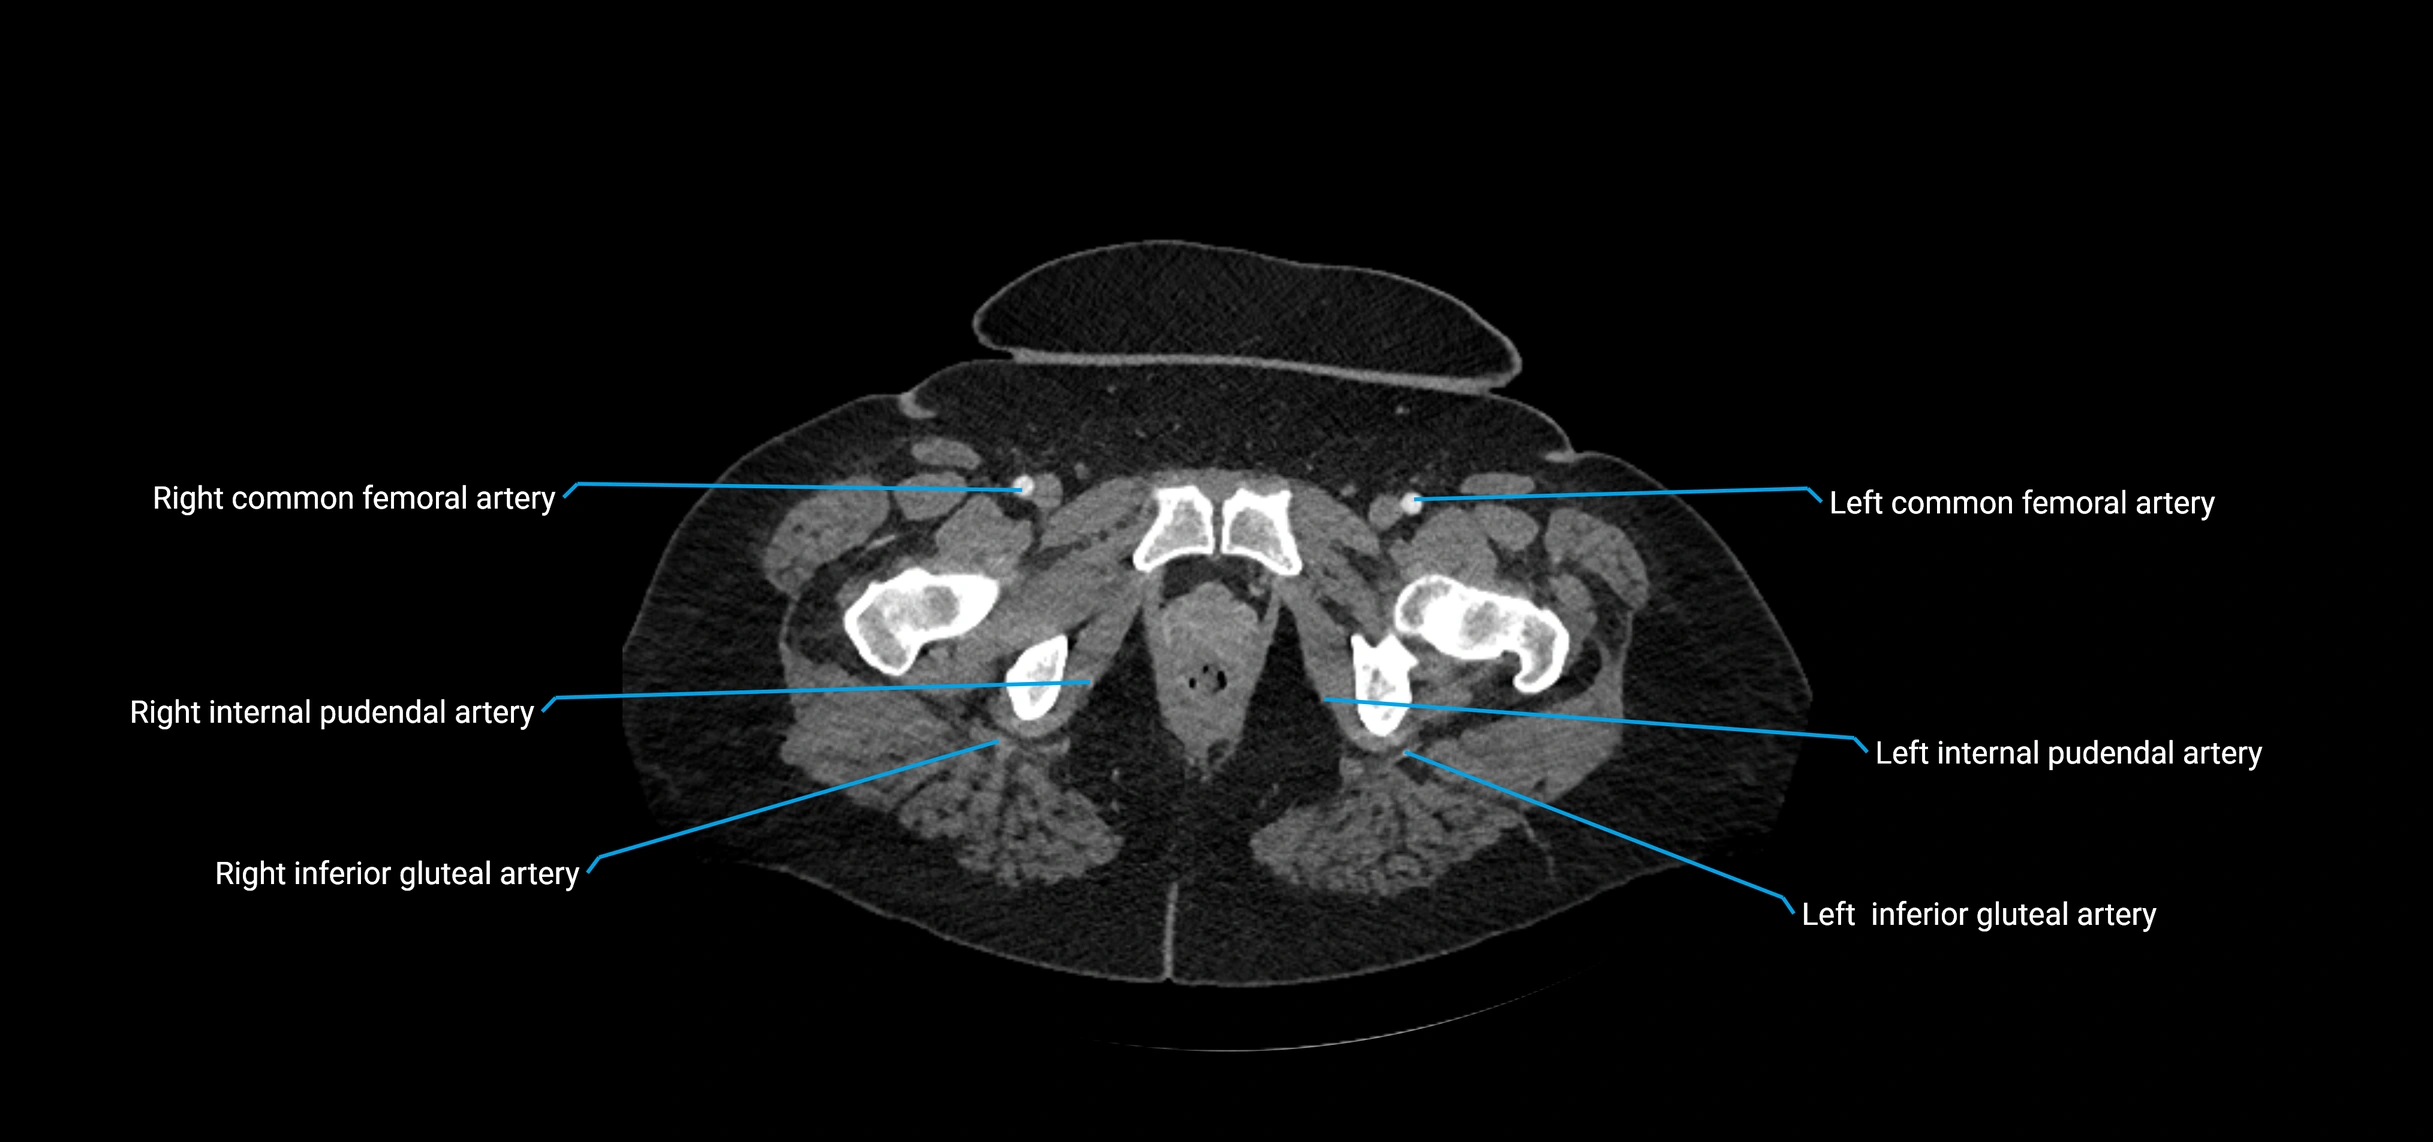

CT Appearance

Non-contrast CT:

• Appears as a tubular soft tissue structure anterior to vertebral bodies

• Calcified atherosclerotic plaques appear as hyperdense foci along the wall

• Useful for screening abdominal aortic aneurysm (AAA) size and mural calcification

Contrast-enhanced CT (CTA):

• Gold standard for abdominal aortic imaging

• Provides excellent detail of lumen, wall, aneurysm, thrombus, and branch vessels

• Multiplanar and 3D reconstructions help in aneurysm measurement, stent graft planning, and dissection evaluation

• Detects acute rupture, traumatic injury, or occlusion with high sensitivity

CT images

image